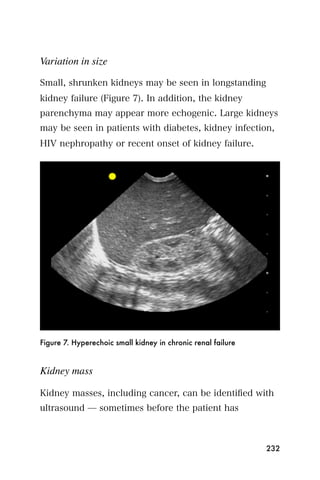

• Baker s cysts can occur in the popliteal fossa and may

be mistaken for a DVT. Like a DVT, a Baker s cyst is

noncompressible but is much larger than a DVT and

can usually be easily palpated without ultrasound.